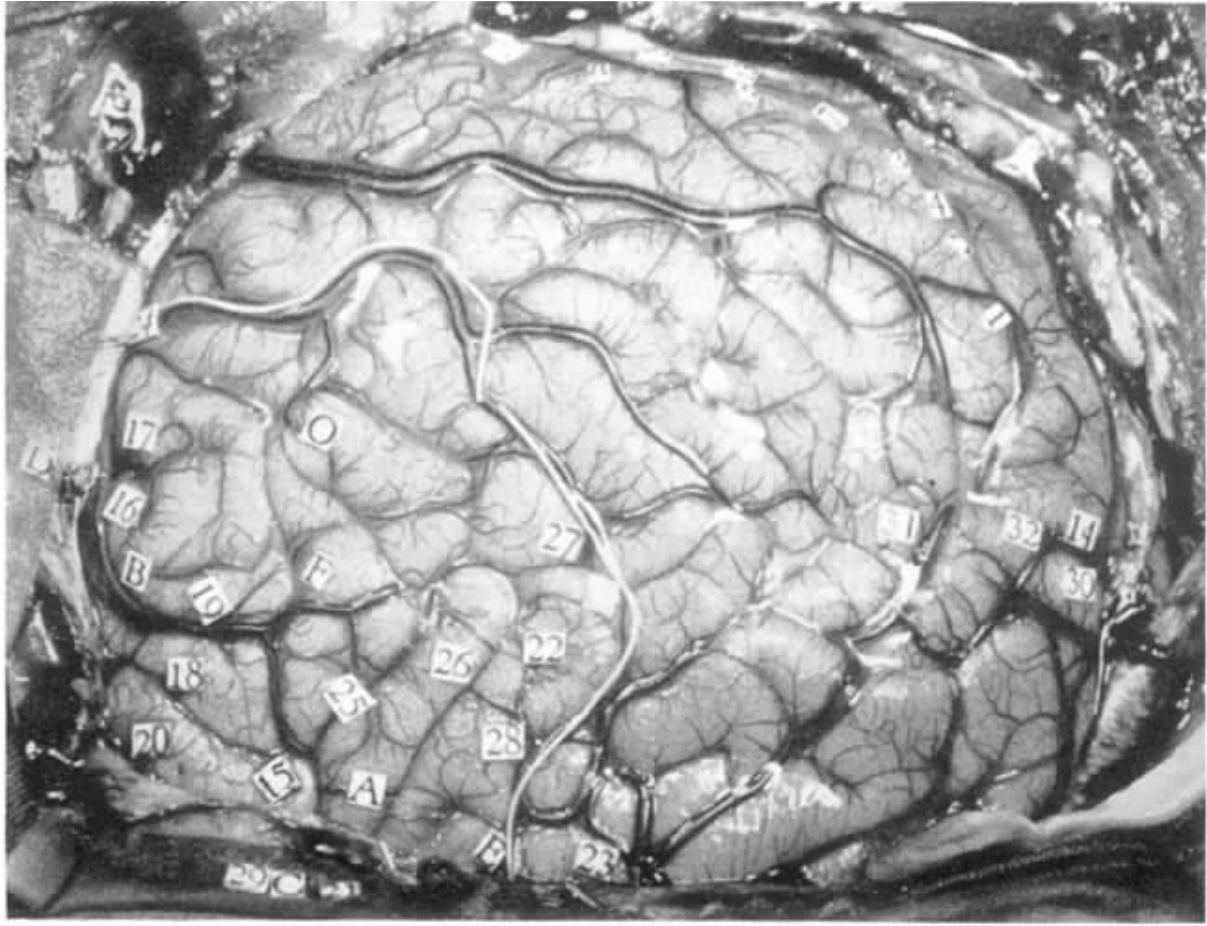

右脑,枕叶视觉皮层,近中央沟处,第一颞回(见图5-1和图5-2)。

电刺激(拉姆刺激仪,60Hz,2V)产生反应的刺激部位如图示,

图5-1 病例R.W.右大脑半球的顶叶、颞叶及枕叶区(枕极见于图中的左下角,白线所标的是将要切除的范围,数字所标的是电刺激后能产生阳性反应的点)

图5-2 病例R.W.数字标示阳性刺激反应(详见文中描述。刺激虚线后面的点能产生视觉反应;在虚线前面的点(点24,22,28,23)能够产生听觉类型的心理性幻想,同发作时类似;刺激点30,31,32,能产生听觉回忆的心理性幻想,但与他平时发作的癫痫无关)